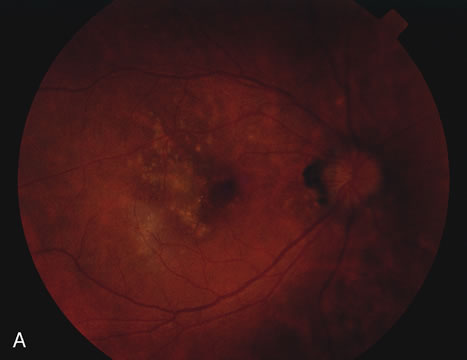

RETINAL FINDINGS

The fundus findings tend to depend on the chronicity of the disease. In new-onset cases, there are just a few choroidal lesions most of which are in the posterior pole. The newer lesions tend to be yellowish-white in coloration and with time they become punched-out. The size of the lesions can be variable ranging from one third to 1 disc diameter in size. They can become confluent and so they may appear larger than the typical size. The newer lesions are associated with visual distortions. Rarely subretinal fluid may be present over fresh choroidal lesions. In addition, choroidal neovascularization may be seen in one third of cases. Subretinal hemorrhage and subretinal fluid should be considered as signs of the development of a possible choroidal neovascular membrane. Retinal phlebitis is rarely present but may be seen as well (Fig. 9).

Fig. 9. A and B. Fundus photographs of the right and left eye showing the classic circular choroidal lesions with marked pigment clumping in a case of multifocal choroiditis.

Fluorescein angiography may show hyperfluorescent spots that increase slightly in the later phases in active lesions. In inactive lesions, these spots become window defects. If there is a choroidal neovascular membrane it is usually seen at the edge of the scar and tends to have classic features. ICG angiography shows hypofluorescent lesions some of which cannot be seen by fundoscopy or by fluorescein angiography. In addition, there may be hypofluorescence surrounding the optic disc in cases of enlarged blind spots in conjunction with multifocal choroiditis.42